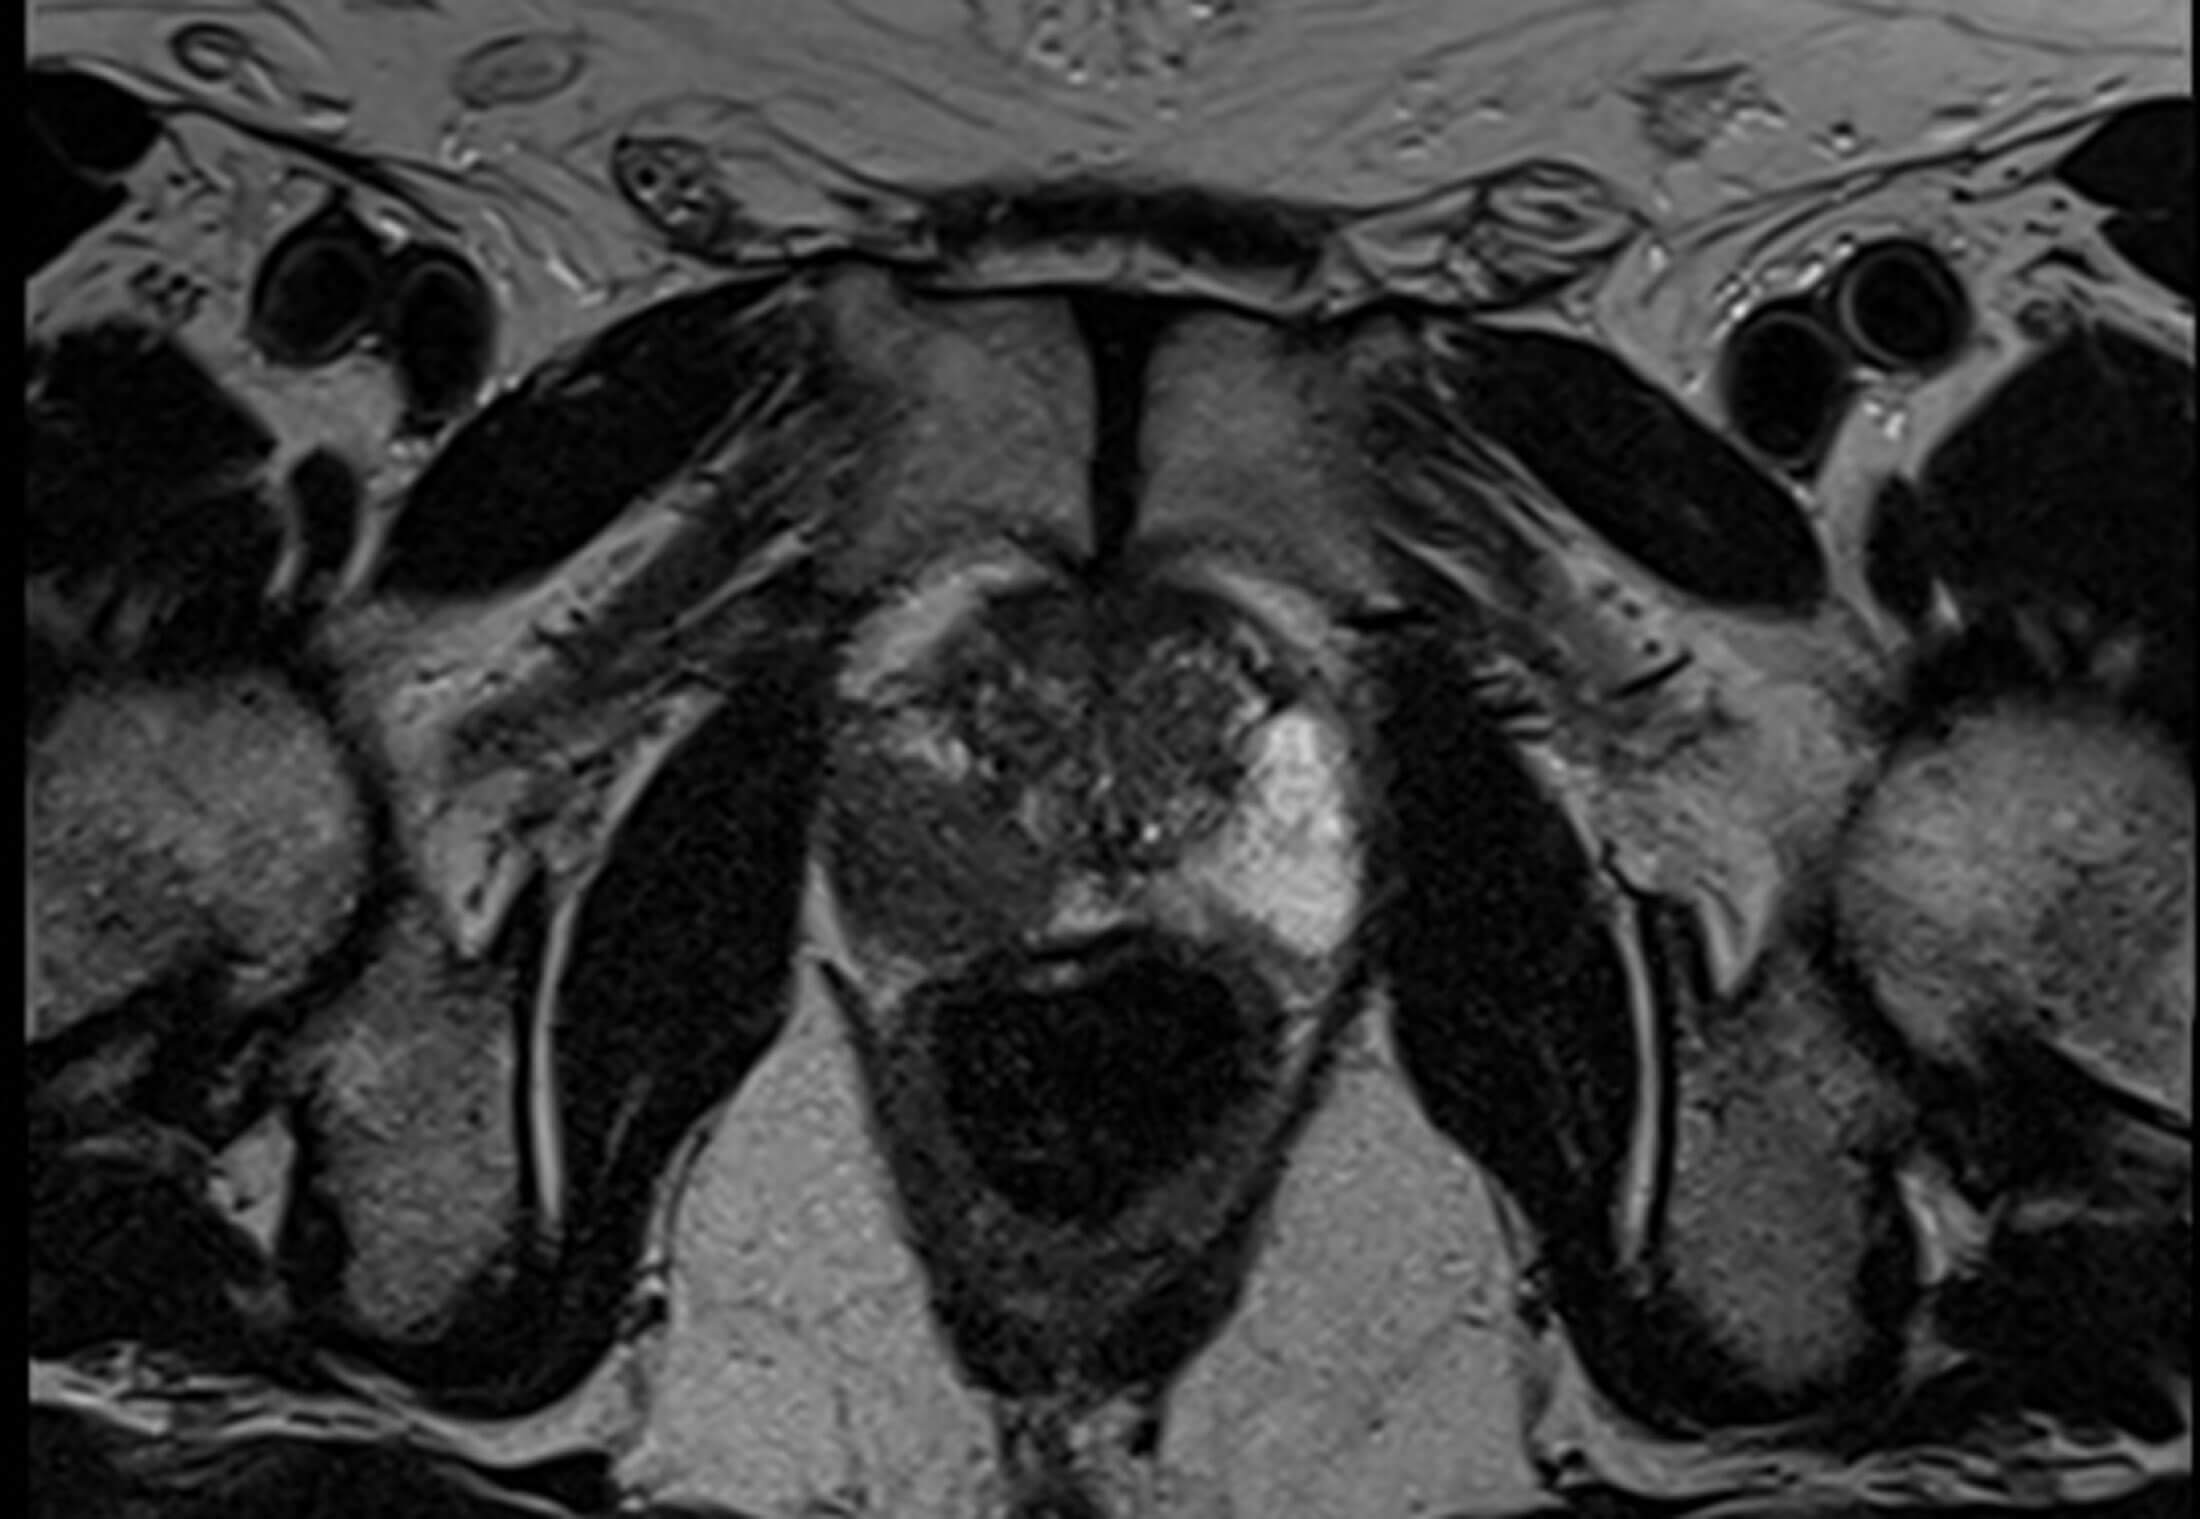

1. Figure 1 is an axial T2 weighted MRI image. It shows an abnormal 3cm lesion in the mid-gland of the right peripheral zone, between 6 o’clock and 8 o’clock. It would be considered T2 N0 M0. Prostate cancer appears dark on T2 weighted imaging [1].